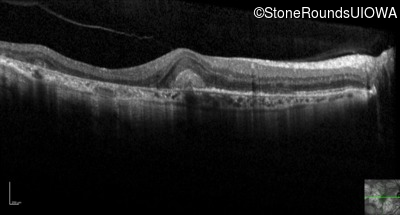

Optical Coherence Tomography - Left - 20/60 sc

Exemplar / OCT Stack